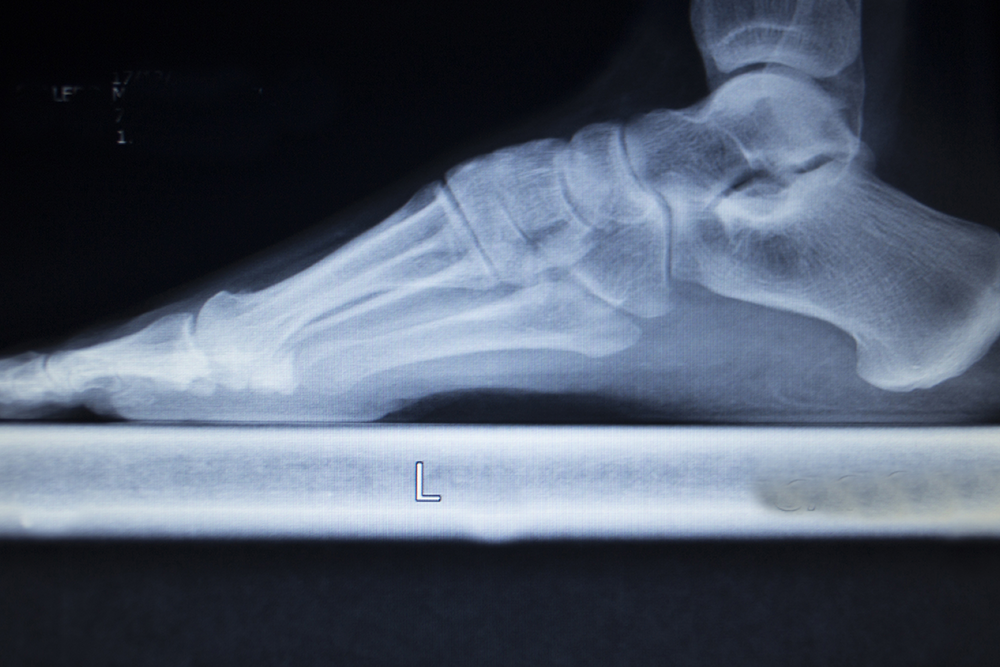

We provide complete foot and ankle care for patients of all ages, including injury treatment, pain relief, diabetic foot management, and preventive care. Our goal is to restore comfort, mobility, and long-term health through personalized treatment plans and advanced diagnostics. Explore the services below to see how we can help you stay active and pain free.